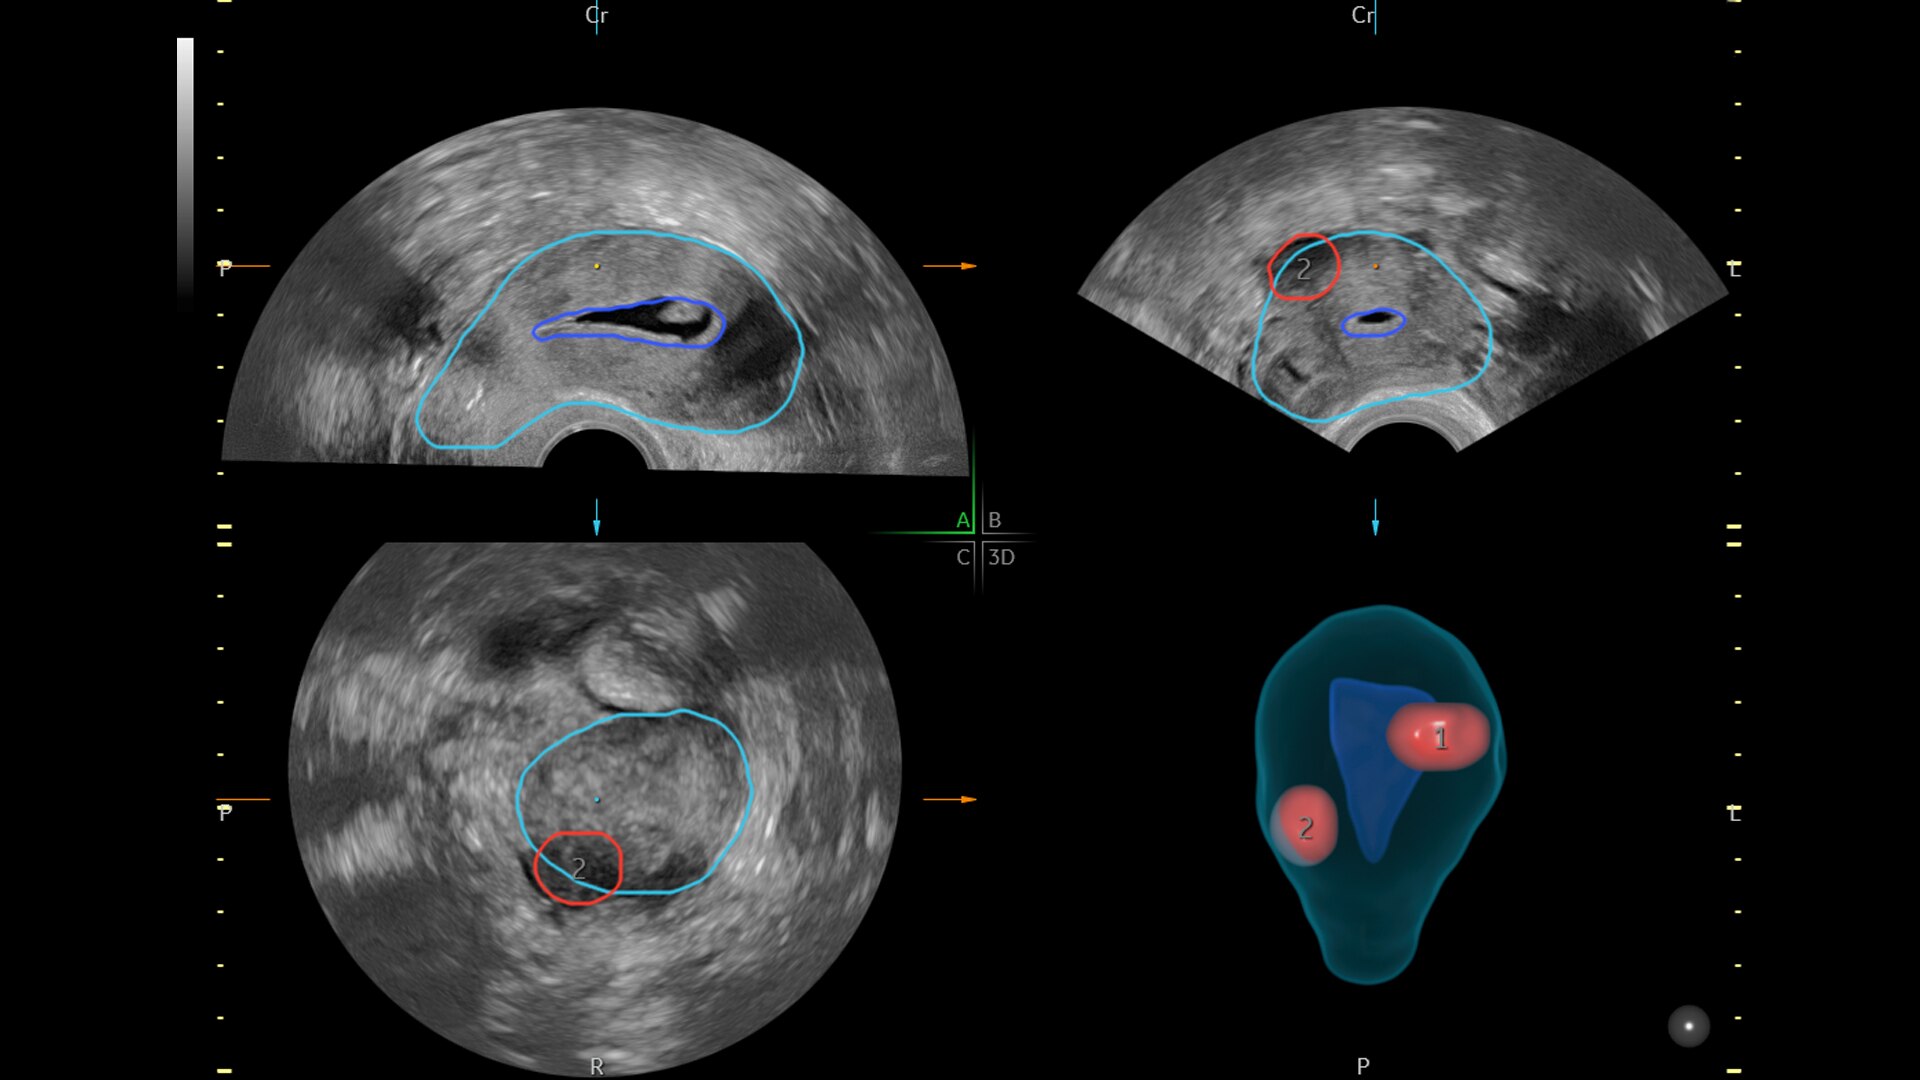

SonoGYN

Combines our Uterine Trace tool and Fibroid Mapping feature, an AI reporting tool that standardizes and streamlines fibroid documentation by mapping, measuring, and classifying fibroids in 3D.

SonoPelvicFloor

Reduce exam time by up to 75% with SonoPelvicFloor. Simplify and speed up exams with automated plane alignment and automated measurements for more consistent reproducible results.